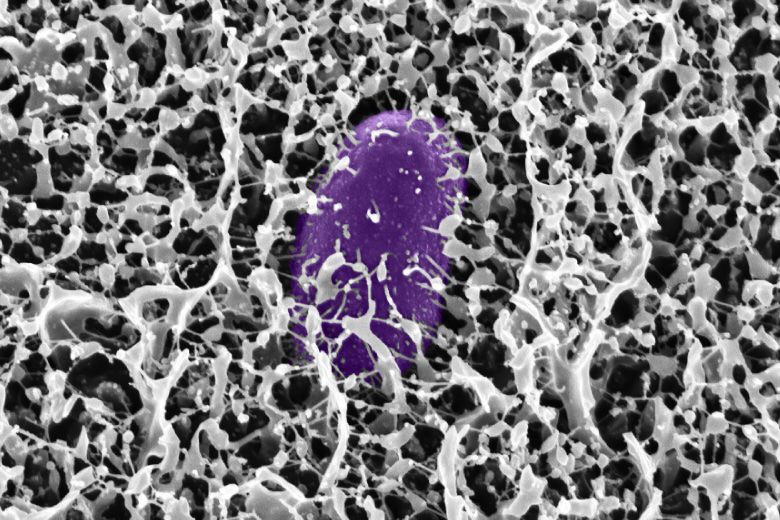

A new study out of MIT shows how mucin found in mucus can be used to stop Salmonella and other viruses before they start. The bottle-shaped polymer can interact with and disarm the genes needed for these illnesses to infect the body.